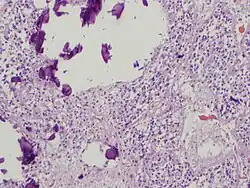

The pineal body in humans consists of a lobular parenchyma of pinealocytes surrounded by connective tissue spaces. The gland's surface is covered by a pial capsule.

The pineal gland consists mainly of pinealocytes, but four other cell types have been identified. As it is quite cellular (in relation to the cortex and white matter), it may be mistaken for a neoplasm.[18]

| Pinealocytes | The pinealocytes consist of a cell body with 4–6 processes emerging. They produce and secrete melatonin. The pinealocytes can be stained by special silver impregnation methods. Their cytoplasm is lightly basophilic. With special stains, pinealocytes exhibit lengthy, branched cytoplasmic processes that extend to the connective septa and its blood vessels. |

| Interstitial cells | Interstitial cells are located between the pinealocytes. They have elongated nuclei and a cytoplasm that is stained darker than that of the pinealocytes. |

| Perivascular phagocyte | Many capillaries are present in the gland, and perivascular phagocytes are located close to these blood vessels. The perivascular phagocytes are antigen presenting cells. |

| Pineal neurons | In higher vertebrates neurons are usually located in the pineal gland. However, this is not the case in rodents. |

| Peptidergic neuron-like cells | In some species, neuronal-like peptidergic cells are present. These cells might have a paracrine regulatory function. |